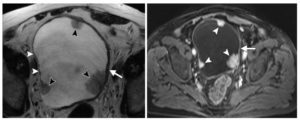

Инфильтративно растущие опухоли мочевого пузыря

а) Т2 cor FS б) Т2-tra

Женщина, 56 лет. Клинически – гематурия, морфологически верифицированная опухоль мочевого пузыря.

На представленных бесконтрастных Т2-взвешенных изображениях в корональной (а) и аксиальной (б) плоскостях видно асимметричное инфильтративное утолщение левой стеки мочевого пузыря, ригидность и уплощение левой стенки на фоне нормального наполнения пузыря. При этом наружный контур инфильтративно утолщенной стенки имеет нечеткие контуры.

Внутривенное динамическое контрастирование, Т1-ВИ, ранняя (артериальная фаза). Видно выраженное диффузное контрастное усиление всей толщины инфильративно измененной левой (и частично задней) стенок мочевого пузыря, с нечеткостью ее наружного контура и признаками минимального экстравезикального распространения.